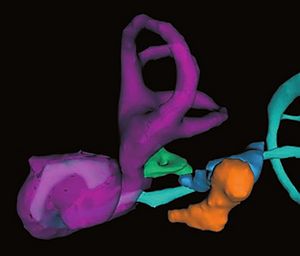

Publication: J Chem Neuroanat. 2016 Jan;71:20-5. PMID: 26686291 Authors: Reinitz LZ, Szőke B, Várkonyi EÉ, Sótonyi P, Jancsik V. Institution: Faculty of Veterinary Science, Department of Anatomy and Histology, Szent István University, Budapest, Hungary. Background/Purpose: We present here a new procedure to represent the 3D distribution of neuronal cell bodies within the brain, using exclusively softwares free for research purposes. Our technique is based on digitalized photos of brain slices processed by immunohistochemical technique, and the 3D Slicer software. The technique presented enables transposition of immunohistochemical or in situ hybridization data to the stereotaxic mouse brain atlas (e.g. Paxinos, G., Franklin, K.B.J., 2001. The Mouse Brain in Stereotaxic Coordinates. second ed. Academic Press, San Diego). By exporting the finalized models into a popular 3D design software (3DS Max) arbitrary environment and motion simulation can be created to improve the visual understanding of the area studied. Application of this technique provides the possibility to store, analyze and compare data - e.g. on the hypothalamic neuropeptides - across experimental techniques and laboratories. The method is exemplified by visualizing the distribution of immunohistochemically identified melanin-concetrating hormone (MCH) containing perikarya within the mouse hypothalamus. |